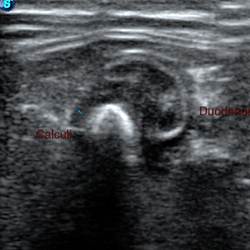

Abdominal ultrasound

Comprehensive exam of the peritoneal and retroperitoneal cavity and its respective organs.